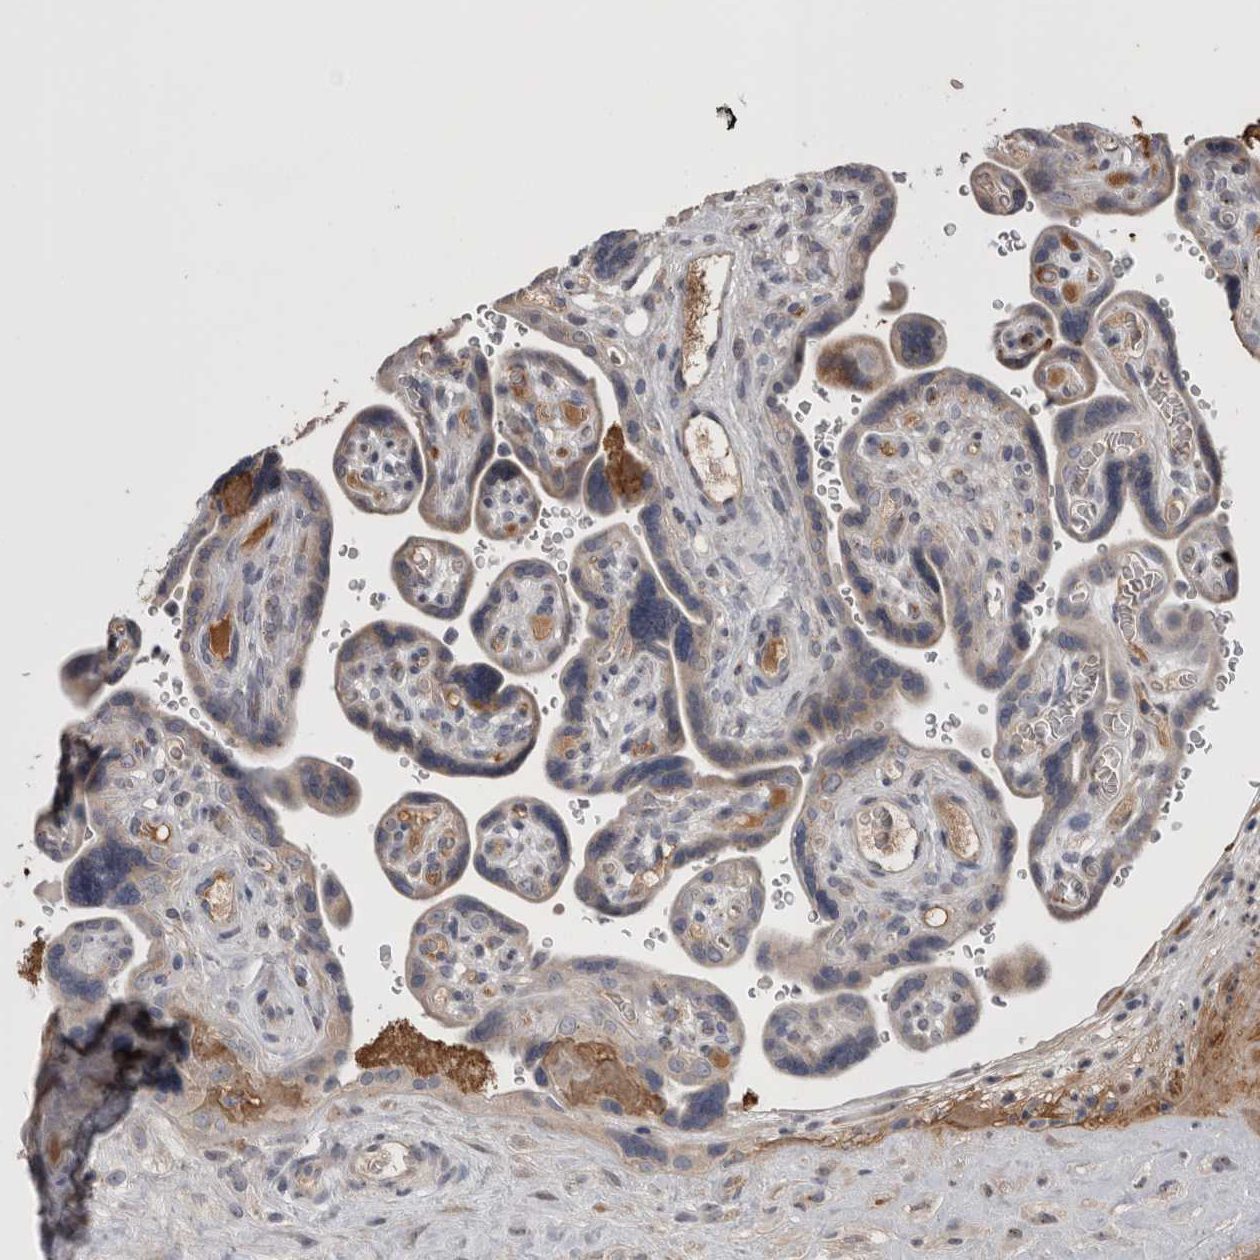

Immunohistochemical staining of human thyroid gland shows moderate cytoplasmic positivity in glandular cells.